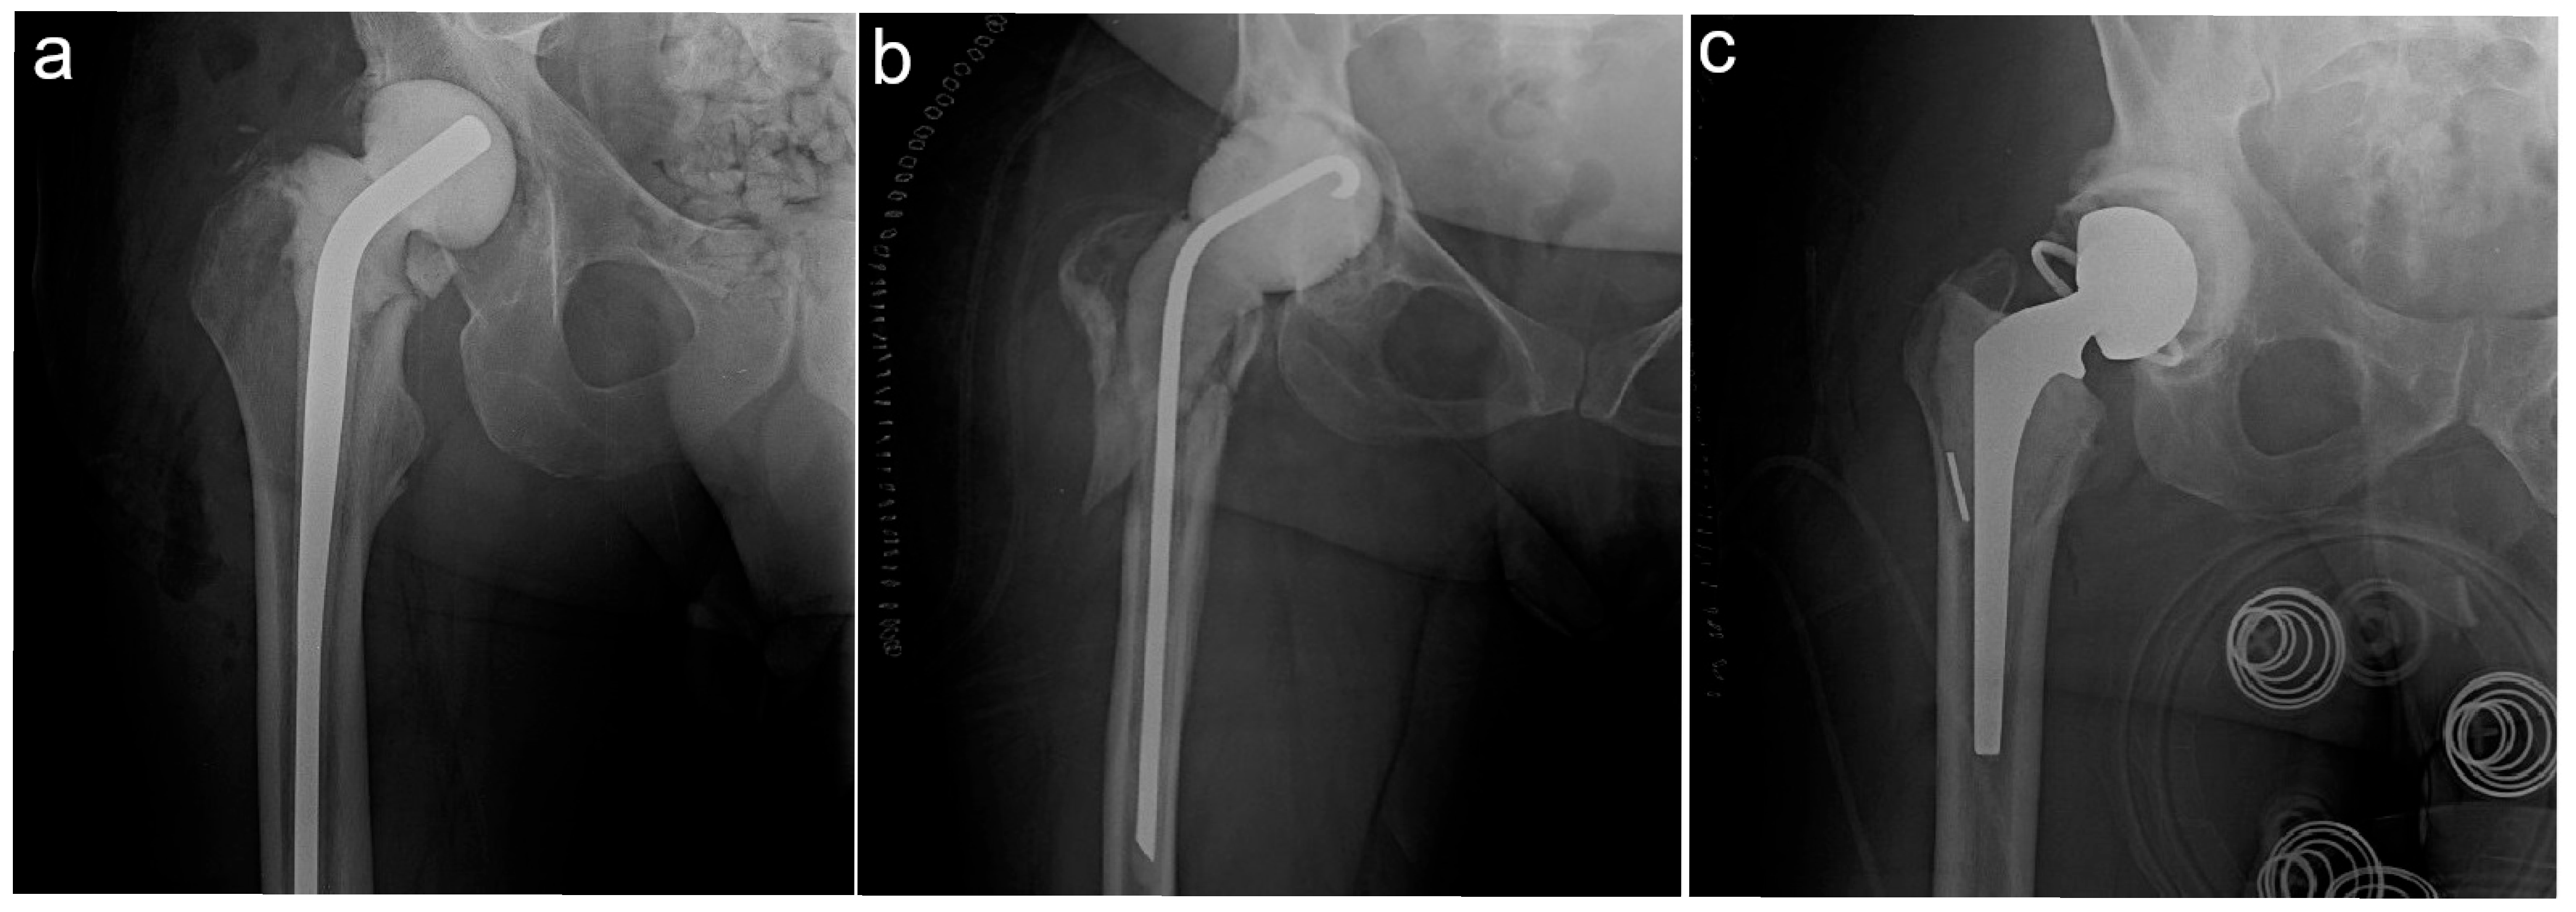

Patients undergoing revision for non-infectious indications, single-stage revisions, acetabular head and/or liner exchange or revisions with stem retention, debridement antibiotic and implant retention (DAIR) procedures, or non-articulating spacer/girdlestone procedures were not eligible. In total, 2039 revision procedures from our institutional databases were reviewed. Seven fellowship-trained arthroplasty surgeons completed the revision surgeries. After excluding 1567 aseptic revisions, 250 single-stage revisions, 47 acetabular liner and/or head exchanges with stem retention, 12 isolated DAIR procedures, and 19 non-articulating spacers/girdlestones, 144 planned two-stage rTHAs remained for final analysis. Spacer characteristics were extracted from the electronic medical record (EMR) and used to stratify patients into three groups: pre-molded hemiarthroplasty (PHA) spacers, custom hemiarthroplasty (CHA) spacers, and custom total hip arthroplasty (CTHA) spacers. Spacer type was selected based on the surgeon’s preference. Pre-molded spacers were manufacturer-prepared and fully formed, while custom spacers were fashioned by the surgeon intraoperatively. Pre-molded spacer types included the InterSpace (Exactech Inc., Gainesville, FL, USA) antibiotic spacer. For all CTHA spacers, a cemented acetabular component was placed, which was either constrained or unconstrained. Custom cemented stem types included Omnifit (Stryker, Kalamazoo, MI, USA), Secur-Fit (Stryker, Kalamazoo, MI, USA), and PROSTALAC (Depuy, Warsaw, IN, USA). The cement used for implantation was mixed with 2 g of vancomycin and 3.6 g of tobramycin per bag of cement. Figure 1 demonstrates the types of spacers used.

Figure 1. The different spacer types investigated in this study. (a) PHA—pre-molded hemiarthroplasty spacer; (b) CHA—custom hemiarthroplasty spacer; (c) CTHA—custom total hip arthroplasty spacer.